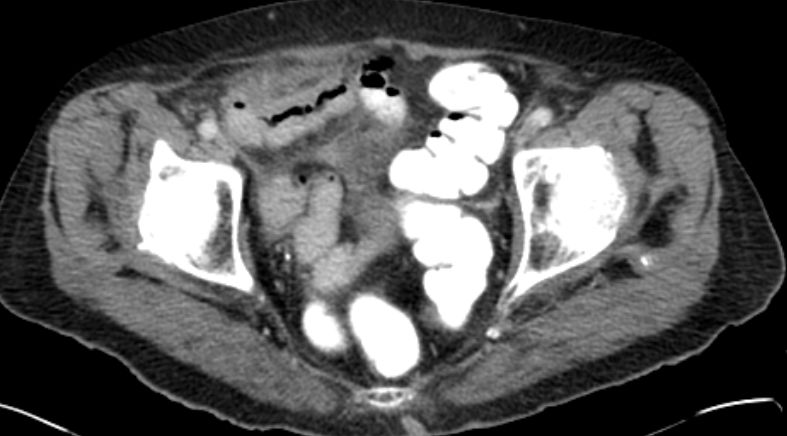

71-jährige Frau mit Adenokarzinom der Appendix pT4b pNo Mo Lo Vo.

Coloskopie: zirkuläres, exophytisch und ulzerierend wachsendes Karzinom mit einer Größe von 60 mm im Colon ascendens, nicht passierbar.![]() |

Unmittelbar oberhalb der Ileozökalklappe Nachweis eines 7 x 6 cm großen, schüsselförmig exulzerierten Tumors.

Der Tumor durchdringt alle Wandschichten und infiltriert retrograd den davor geschalteten Dünndarm.![]() |